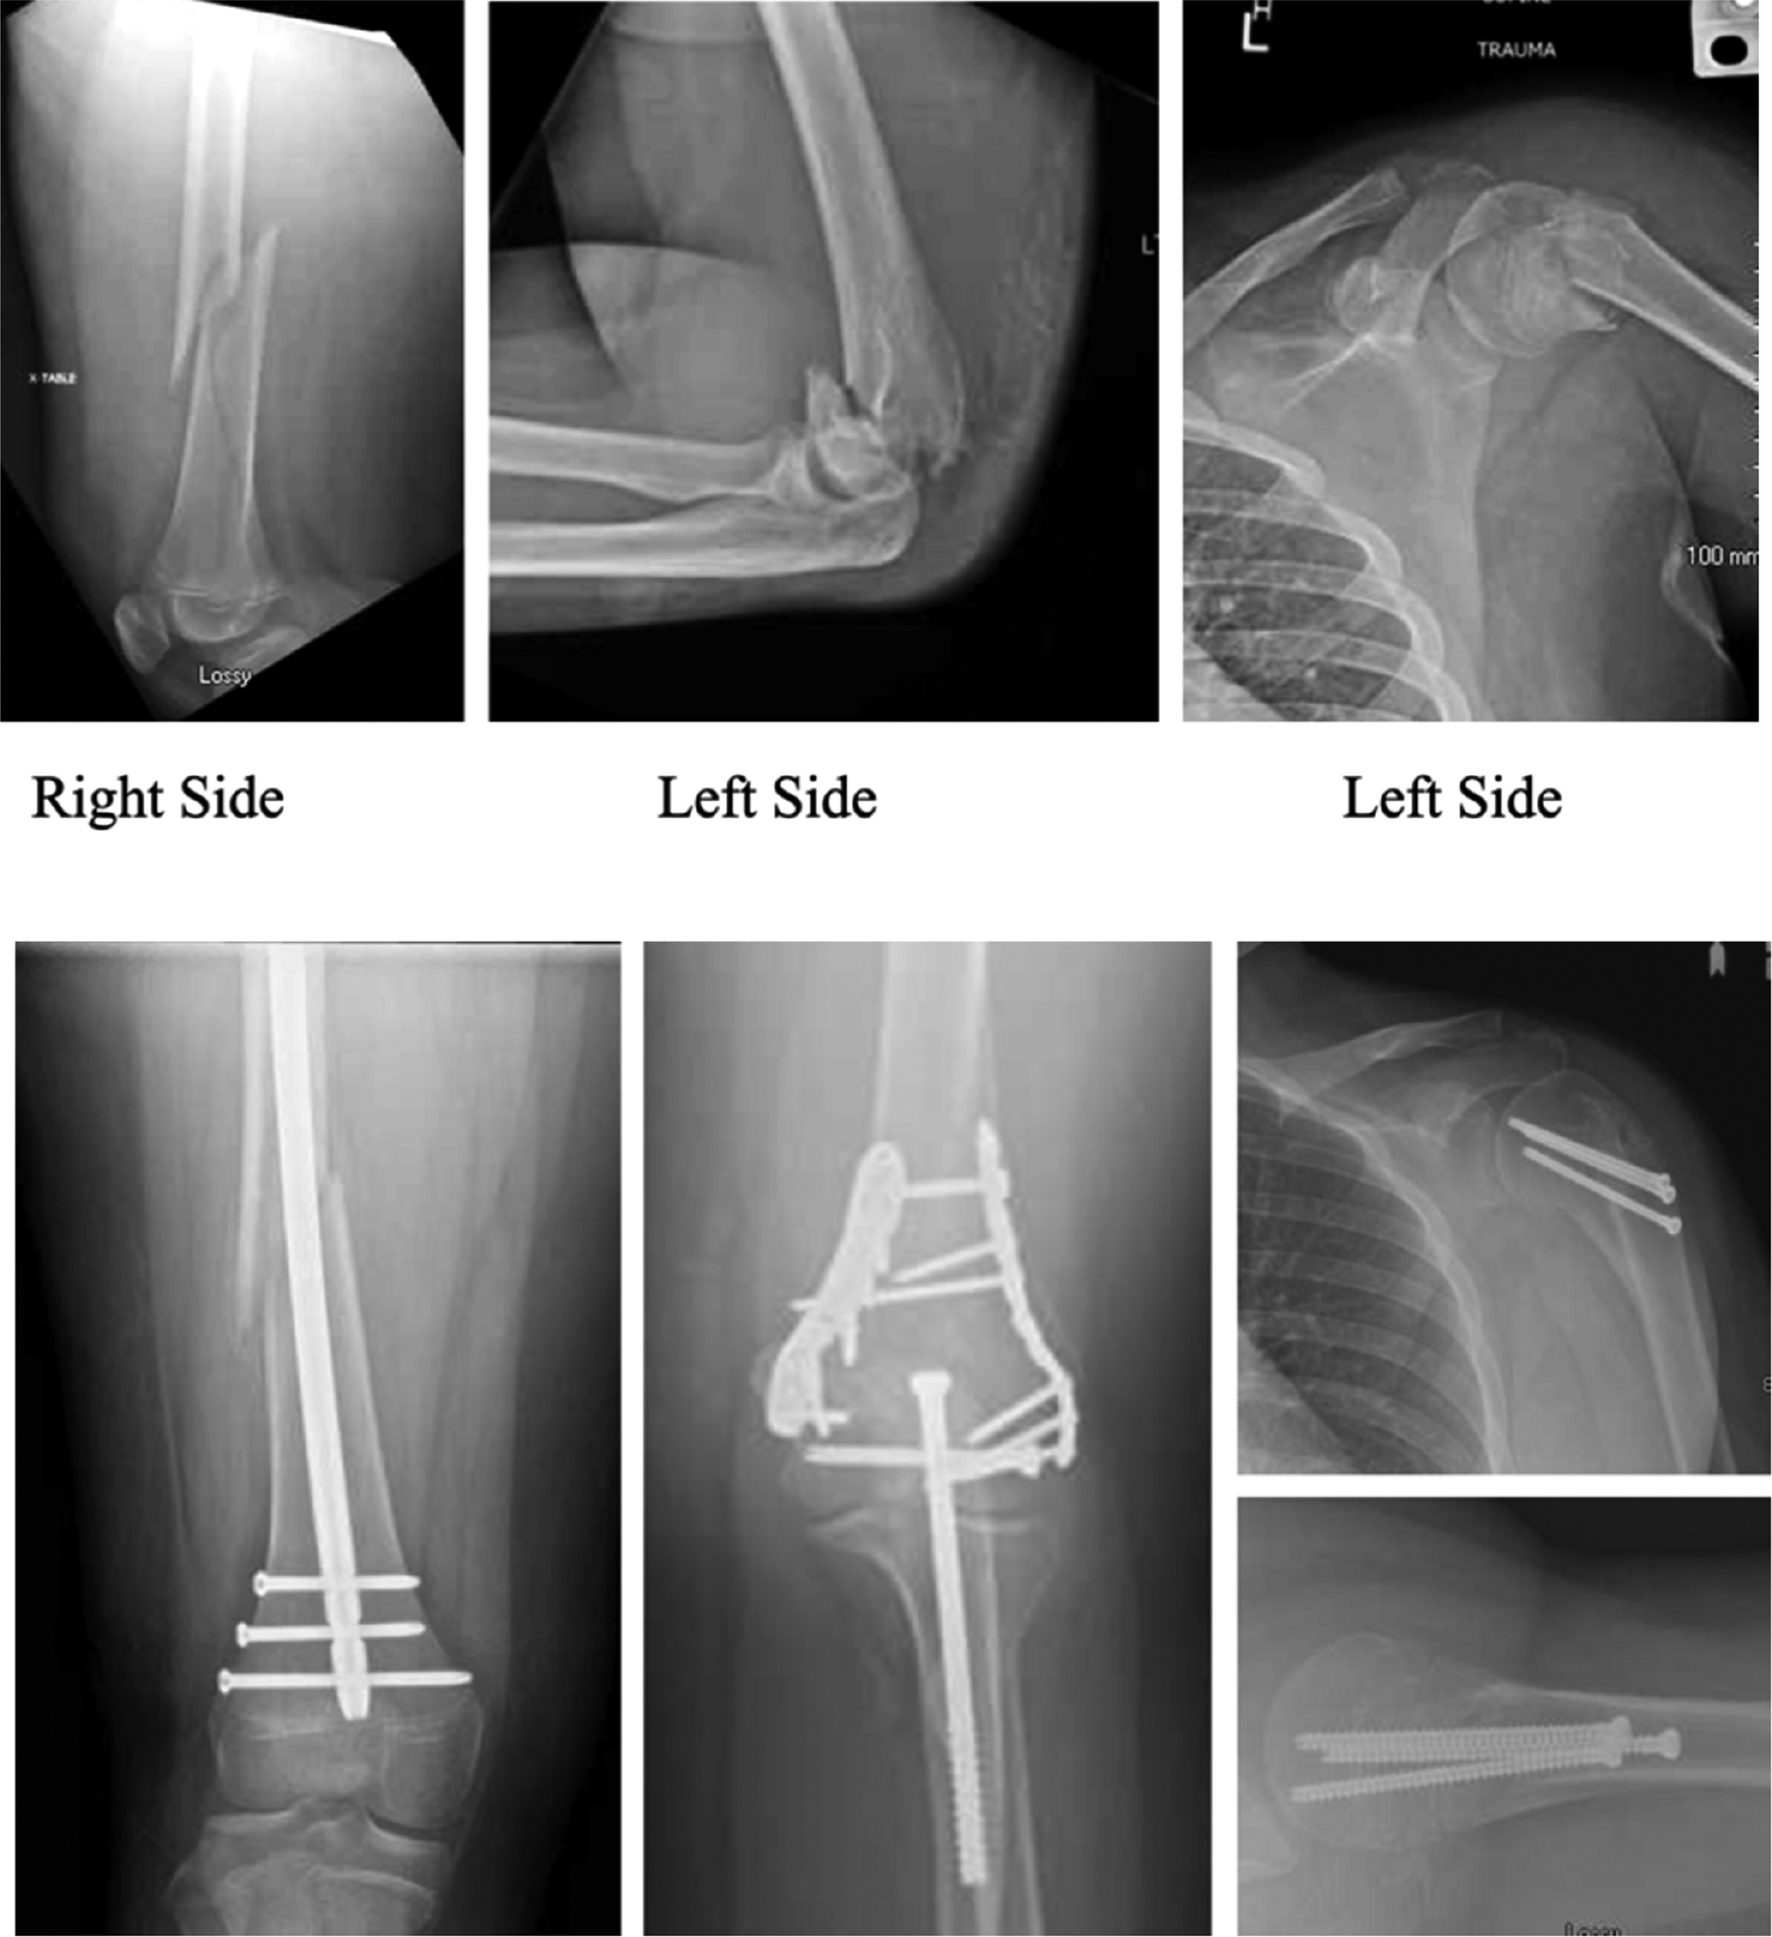

In some cases, recommendations are clear. For example, patients with associated injuries such as open fractures, vascular injury, and polytrauma are usually managed surgically given the concomitant injury and in order to minimize risk of complications (Figure 4).36 In contrast, for obstetric fractures, the treatment is uniformly swaddling with excellent outcomes.7,29 The guiding principle is nonoperative management in younger children and a lower threshold to operate in adolescents with impending closing physes. Overall, there has been a decreasing rate of operative management of adolescent proximal humerus fractures in recent years with considerable geographic variation.6 There is also difference in management depending on the treating hospital with higher rate of operative management in general hospitals compared to children’s hospitals which demonstrates this lack of consensus.5,6

Figure 4. This is a 14-year-old patient who was injured when his ATV ran into a barn. Operative fixation of all three fractures was performed. Case courtesy of Ken Noonan, MD.